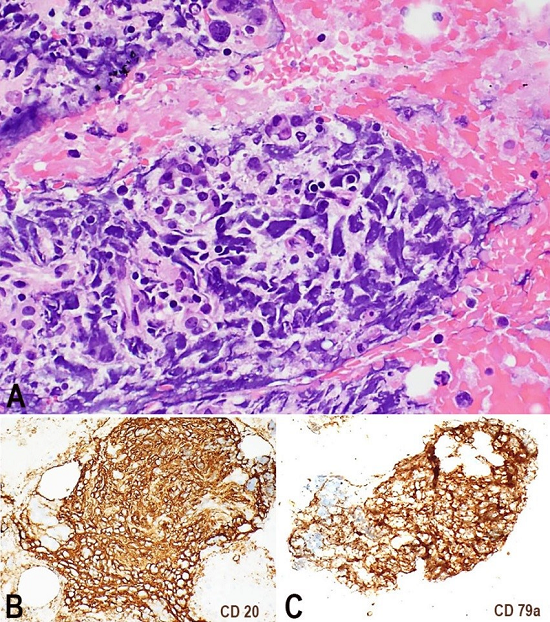

A 71-year-old Caucasian female had a past medical history of arthritis, central serous retinopathy, remote deep vein thrombosis (not on anticoagulation), hyperlipidemia and osteoporosis. She presented with a 3-month history of fatigue, abdominal pain and loss of appetite. She was referred to the emergency room after an outpatient work-up for gradual progression of fatigue and anemia. She had a hemoglobin of 10.7 g/dL (reference value [RV]: 13.7-17.5 g/dL), mild thrombocytopenia and abnormal liver function tests. During her hospital admission, she was afebrile with the following vital signs: pulse 110 beats/minute, blood pressure 115/80 mmHg, and O2 saturation of 95% on room air. Her notable lab values were Na+ 128 mmol/L (RV: 134-146 mmol/L), AST 110 U/L (RV: 15-56 U/L), ALT 73 U/L (RV: 11-50 U/L), GGTP 94 U/L (RV: 3.0-28.7 IU/L) and albumin 2.6 gm/dL (RV: 3.5-5.0 gm/dL). The abdominal computed tomography suggested hepatic and portal vein thrombosis, with suspicion of hepatitis, pancreatitis, and colitis. On magnetic resonance imaging, right hepatic vein thrombosis and a 1.9 × 1.8 cm lesion in the pancreatic tail was noted; based on the imaging studies, a pancreatic carcinoma or a pancreatic neuro-endocrine tumor was suspected. A CT-guided needle core biopsy on the pancreatic tail mass showed multiple foci of large frankly neoplastic cells infiltrating normal-appearing pancreatic lobules featuring scant cytoplasm, nuclei with regular contour and prominent nucleoli; mitotic figures and numerous apoptotic bodies were noted. Extensive immunohistochemical work-up was unrevealing and proliferation index by Ki-67 was high (>95%). Ultimately, the patient was given a diagnosis of diffuse large B-cell lymphoma (DLBCL) on the concomitant cytology specimen, which was the actual diagnostic material. The cell block showed highly atypical large cells intermixed with pancreatic acini. Those cells were positive for CD20, CD79a, and CD45, and focally PAX-5 (Figure 1). Stain for MUM-1 was non-contributory, and a further sub-classification could not be performed. Subsequent bone marrow aspirate and biopsy showed no involvement.

The portal vein thrombosis was related to neoplastic involvement, as the thrombus was predominantly composed of neoplastic lymphocytes. The neoplastic lymphoid cells were larger in size with large pleomorphic nuclei and irregular prominent nucleoli. Some anaplastic cells were seen with larger more atypical features. The tumor burdens were largely within the vasculature. CD20, PAX5, CD5, CD10, MUM1, CD3, and Ki-67 immunohistochemistry stains were obtained on the pancreatic mass (Figure 3) and the lung tissue (Figure 4). The malignant cells were positive for CD20 (strong), MUM1 (weak), Pax-5 (weak) and CD5, and were negative for CD3 and CD10. Ki-67 showed a high proliferative index (>90%). The Epstein-Barr encoding region in situ hybridization was negative.

The pancreatic lesion described here with extravascular extension into the pancreatic parenchyma (as shown in Figure 3) is uncanny. We believe this represents a feature not previously described in other cases of IVLBCL. Apart from that, our case is indistinguishable from other IVLBCL, albeit we found other unusual features such as large vessel involvement, including portal vein and pulmonary arteries, and the infiltration of para-esophageal and para-aortic lymph nodes. It is to be noted that CD5+ DLBCL often presents with low-level blood involvement, as well as visceral involvement of the liver, spleen, and bone marrow, which begs the question of a possible relationship reflecting the spectrum of a disease with common lymphomatous origin.